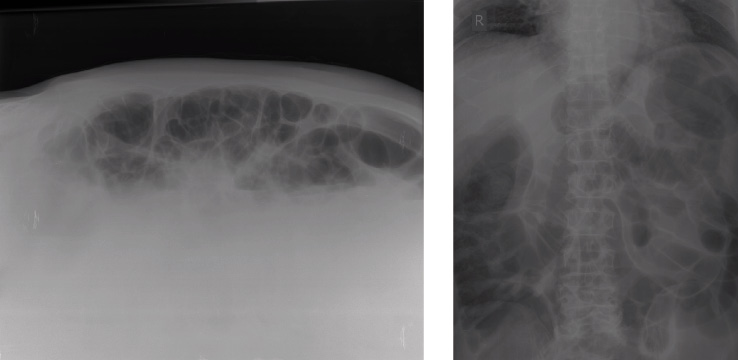

Nella terza giornata postoperatoria si rileva la comparsa di alvo diarroico accompagnato da febbricola. All’esame obiettivo si riscontra un addome globoso, trattabile ma dolente alla palpazione profonda con notevole meteorismo diffuso. Viene richiesta ed eseguita una consulenza geriatrica, a seguito della quale si effettuano un esame parassitologico e colturale delle feci, un Rx diretto addome (Figura 1) e un’ecografia addominale. Inoltre, viene consigliato di aggiungere alla terapia antibiotica rifaximina 2 compresse 2/die, oltre alla somministrazione di loperamide 1 compressa 3/die e all’assegnazione di una dieta povera di scorie.

Figura 1. Rx diretto addome in decubito supino che evidenzia una marcata iperdistensione delle anse tenuali e coliche con livelli idroaerei nel contesto. È presente una coprostasi colica